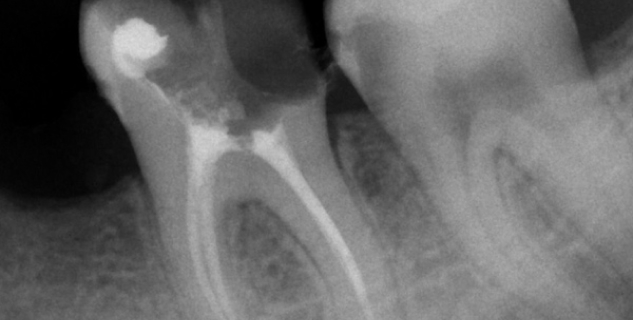

• Наши аппараты воздействуют только на пораженную ткань, не затрагивая здоровую область. Искривленные корневые каналы обрабатываются гибкими Ni-Ti инструментами.

• Радиовизиограф позволяет выявить количество, длину, строение каналов, качество их прочистки, плотность заполнения пломбировочным составом.